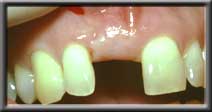

Deficient ridge making artificial tooth look unnatural |

Ridge augmented and expanded so artificial tooth appears to emerge from gum |